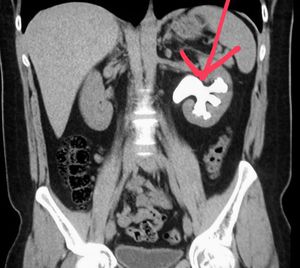

Large kidney stone

Abdominal CT shows a large stone (staghorn calculus) of the kidney in a patient with blood in the urine and pain.